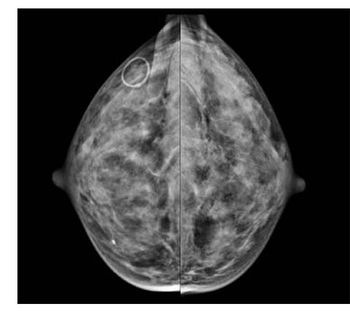

Case History: 52-year-old female presented with a palpable, tender mass in the left breast.